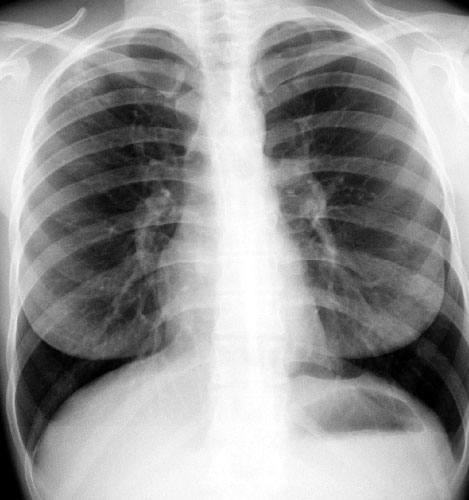

Рентген грудной клетки

Если человек заразился туберкулезом, но не развилось активное заболевание, рентгенограмма грудной клетки часто будет нормальной. У большинства людей с положительным PPD (кожным тестом) или анализом крови на ТБ рентген грудной клетки нормальный, и они остаются здоровыми. Таким людям могут быть рекомендованы профилактические препараты.

Однако, если микроб атаковал и вызвал воспаление в легких, на рентгеновских снимках грудной клетки может быть видна ненормальная тень. Этим людям часто подходят диагностические тесты (анализ мокроты) и лечение. Узнать больше.